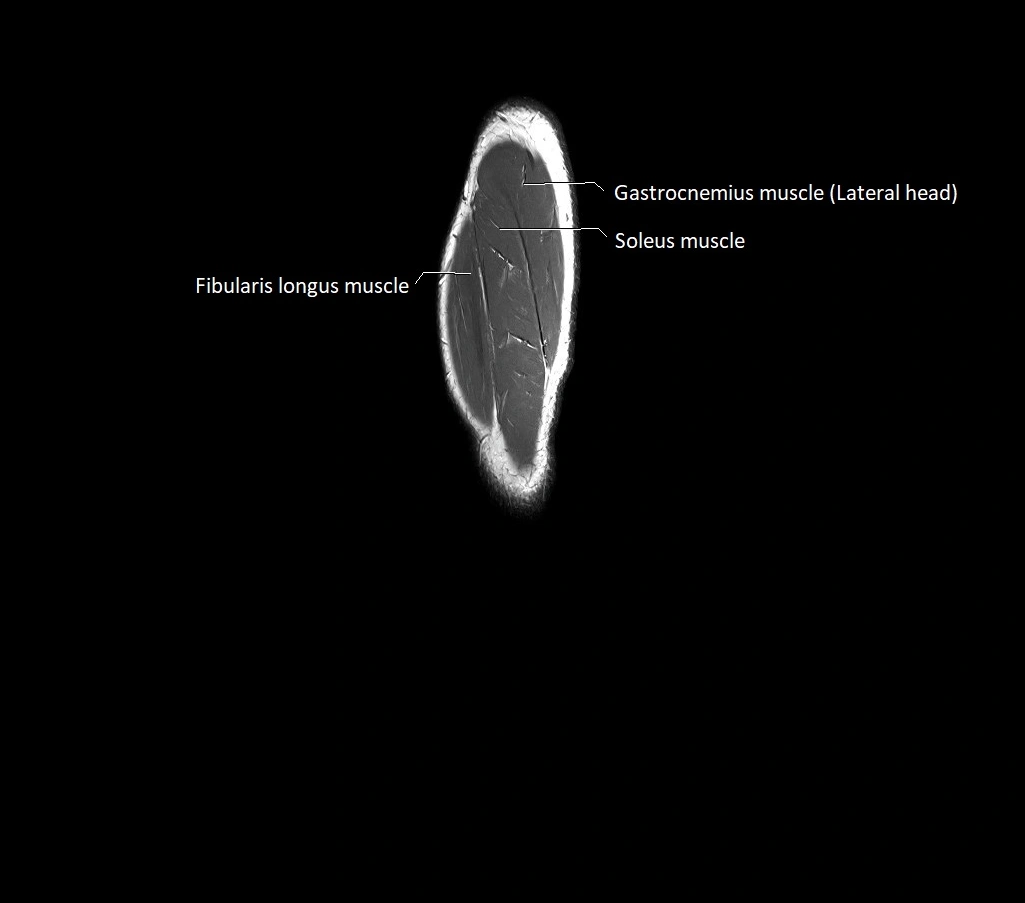

MRI image